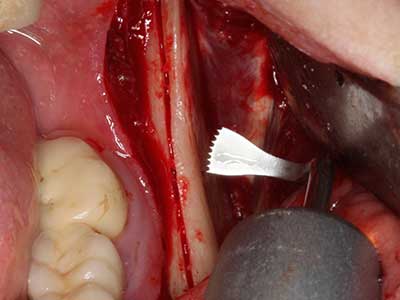

When surgical procedures are performed on bone in the immediate vicinity of sensitive structures such as blood vessels or nerves, rotary instruments pose a significant risk of iatrogenic injury. Piezoelectric devices can be helpful for preparation of bone covers and removal of hard tissue close to nerves, particularly for exposure of nerves after iatrogenic injury but also during nerve lateralization for resective and reconstructive procedures or implant placement (Fig. 17-20). Light contact between the piezotip and the nerve does not generally result in damage but proceeding incautiously with saw-like motions or attachments where a residual bone substrate remains may cause temporary or even permanent nerve damage. However, the risk of damage is considered to be substantially lower than when using saws or milling instruments (Pereira, Gealh et al. 2014).